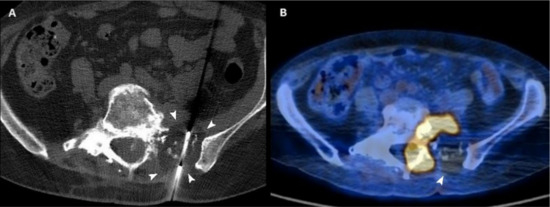

Figure 3.

(A) Axial CT scan of a 54-year-old woman with a sacral metastasis from endometrial sarcoma treated with cryoablation for palliative intent. The ice ball is visible as a hypodense circle surrounding the tip of the needle (arrowheads). (B) 18F-FDG PET/CT scan performed 3 months after the procedure demonstrates the absence of pathologic radiotracer uptake in the ablated area (arrowhead).